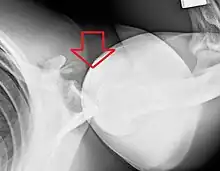

Anterior dislocation of the right shoulder. Y view X ray.

Fracture dislocation of the right shoulder